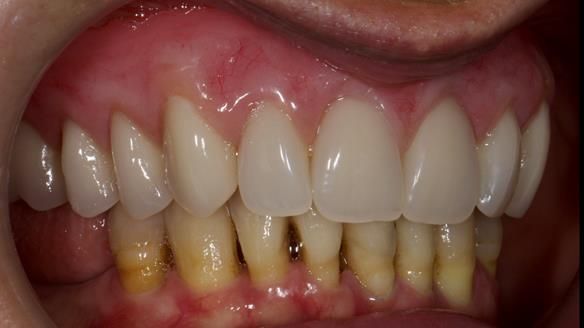

We provided her with an immediate upper denture (Mk 1), followed by a definitive metal-based upper denture (Mk 2). A lower removable partial denture was discussed, to be made only if needed once the upper treatment was complete. However, at review, this wasn’t necessary — Adnana had excellent neuromuscular control and function, even with a shortened dental arch (SDA).

Rowan, Sam Hesketh and Chris Hesketh provided the stunning technical work. I am very lucky to have them.

- A restored smile, restored lip support, and a patient who owned the journey